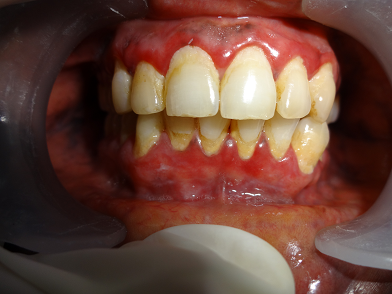

aphthous ulcers

desquamative gingivitid